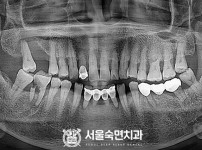

임플란트-전후사진3